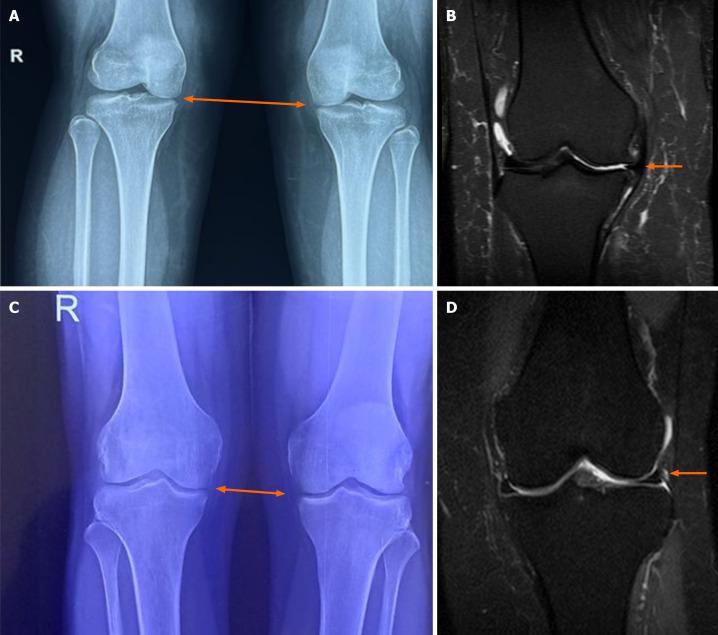

The study included 50 patients with Kellgren-Lawrence grades II and III OA. Patients were randomly assigned (1:1) to receive either a single intra-articular SVF injection (group A) or a single intra-articular ICS (triamcinolone) (group B) injection. Patients were followed up at 1, 3, 6, 12, and 24 months. Visual analog score (VAS) and International Knee Documentation Committee (IKDC) scores were administered before the procedure and at all follow-ups. The safety of SVF in terms of adverse and severe adverse events was recorded. Statistical analysis was performed with SPSS Version 26.0, IBM Corp, Chicago, IL, United States.

该研究纳入了50例Kellgren-Lawrence分级为II级和III级的骨关节炎患者。患者被随机分配(1:1)接受单次关节内SVF注射(A组)或单次关节内ICS(曲安奈德)注射(B组)。在1、3、6、12和24个月对患者进行随访。在手术前及所有随访时进行视觉模拟评分(VAS)和国际膝关节文献委员会(IKDC)评分。记录SVF在不良和严重不良事件方面的安全性。使用美国伊利诺伊州芝加哥市IBM公司的SPSS 26.0版本进行统计分析。